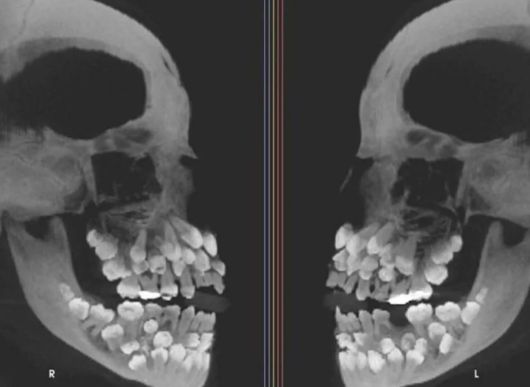

소녀의 치아는 총 81개로 세계적으로 드문 사례다.

15일(현지시간) VN익스프레스 등 외신에 따르면, 브라질 미나스제라이스주에 사는 소녀는 유치를 뽑기 위해 치과를 찾았다가 엑스레이 사진을 보고 충격 받았다. 아직 나지 않은 치아를 포함해 모두 81개가 있었기 때문이다.

그런데 이 소녀는 유치 18개에 영구치 32개, 과잉치가 31개였다.

소녀를 진료한 병원 연구진은 “이런 상태는 ‘다발성 과잉치증’”이라며 “과잉치는 보통 한두 개 생기는데, 30개가 넘는 경우는 거의 없다”고 설명했다.